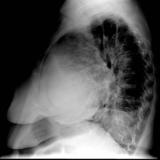

Case 1 Lat

Date: 03/17/2004

Views: 2983